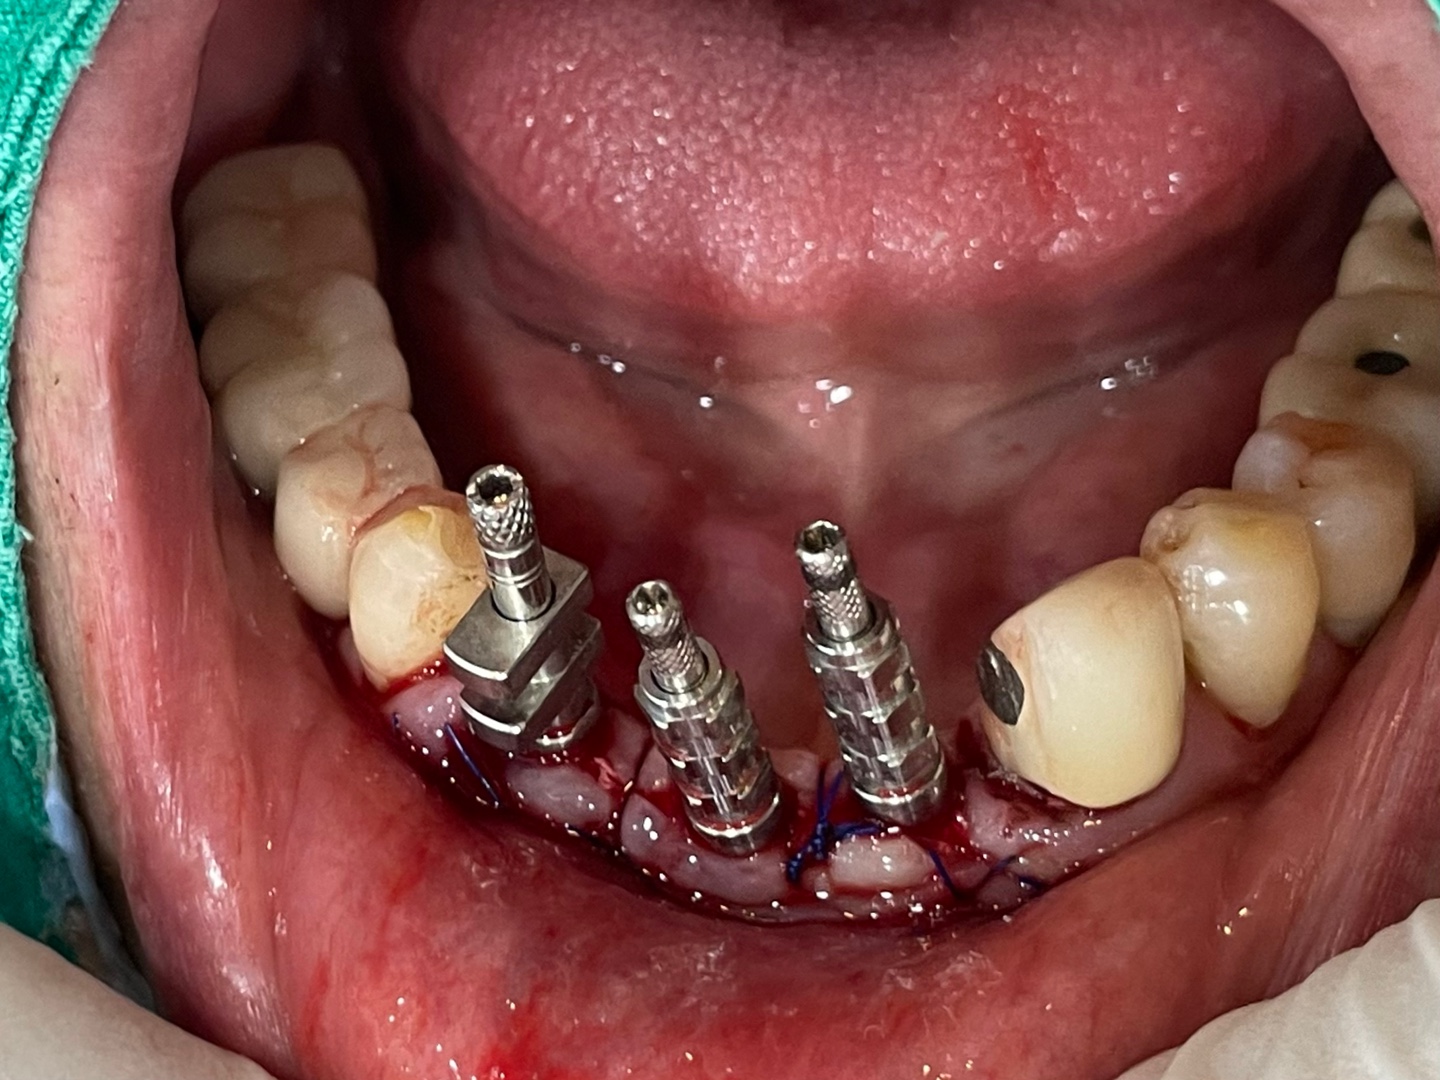

수면마취후 수술을 권해 드렸고 즉시 부하로 최대한 빨리 5일정도면 예쁜 고정성 임시치아가 가능하다고 말씀드렸습니다.

지난 금요일 오후에 수술을 시행하고 다음 수요일에 치아를 넣어 드렸습니다. 임시 치아라 밝은 느낌은 있었지만 추후 수정 가능하다고 말씀드렸습니다. 치아가 자연스럽게 잘 나와서 서로 기분이 좋았던 증례입니다.

환자분 오랬동안 아래 송곳니 쪽이 붓고 불편했지만 끝까지 치료를 미루어 오시다가 수면마취와 즉시 부하로 잘 고민이 해결되었습니다.

저희 병원은 완전히 불편감은 없애드리지 못하지만 최대한 일상에 지장이 없도록 최선의 노력을 기울이고 있습니다.